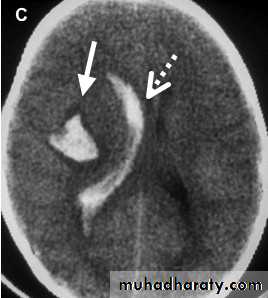

• Cerebral haemorrhage in the acute stage will show up as white. Small haemorrhages may resolve quickly and, even within a few days, they may look similar to infarction. (Figure 1c).

• Figure 1c: Intracerebral haemorrhage in the right hemisphere (solid arrow) with some blood in the right lateral ventricle (broken arrow.)